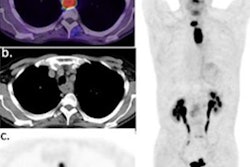

In this scientific talk, researchers will compare the performance of F-18 FDG and F-18 fluoroethylcholine in preoperative lymph node assessment of breast cancer patients on PET/MRI.Dr. Nina Poetsch from the Medical University of Vienna will discuss her team's results. They analyzed pretherapeutic PET/MRI scans, using histology through surgical excision or biopsy as the ground truth. A total of 87 breast cancer patients were matched according to age, tumor size, histologic subtype, and molecular subtype. Out of these, 40 were placed in the FDG group, with 18 positive lymph nodes found. The other 47 were in the FEC group, with 21 positive lymph nodes found.

The team found that the area under the curve (AUC) in the F-18 FDG group was 0.821 for finding metastatic lymph nodes for cortical diameter and 0.844 for visual T2-weighted evaluation. Also for this group, the AUC for the maximum standardized uptake value (SUVmax) was 0.852 and 0.801 for visual PET evaluation (p > 0.05).

In the F-18 FEC group, the AUC was 0.791 for cortical diameter, 0.711 for visual T2w evaluation, 0.821 for SUVmax, and 0.847 for visual PET evaluation (p>0.05).